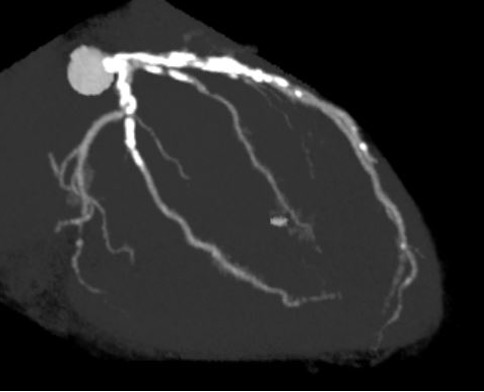

Resting ECG showed ST-segment depression in leads V5–V6. Echocardiography demonstrated preserved left ventricular systolic function with an ejection fraction of 67%. Laboratory tests showed normal renal function and a normal BNP level. Coronary CT angiography revealed severe calcification in both the LAD and left circumflex arteries.

Coronary angiography via the radial approach showed a severe proximal LCx stenosis and a long, severe mid-LAD stenosis, while the RCA had no significant disease. IVUS of the LAD demonstrated diffuse calcification and an eccentric calcified plaque protruding from the septal side near the diagonal branch bifurcation. The guidewire was biased toward the diagonal branch, causing tenting of the relatively healthy wall at the most critical segment.